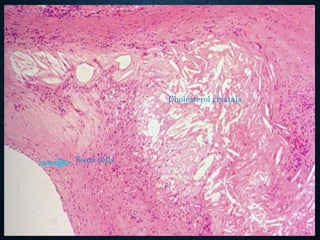

DYSTROPHIC CALCIFICATION

• Deposition takes place in dead or dying tissues, or

dystrophically altered tissues that have a reduced

metabolism.

• The level of serum calcium is normal, and the deposition is

conditioned by a special property of the tissue.

• in areas of necrosis

• dead fetus-lithopedion

• extinct parasites (trichinella or echinococcus)

• hyalinized connective tissue or scar

• in altered heart valves (rheumatic endocarditis)

• atheroma

• thrombi (phleboliths)

• Mönckeberg's medial calcifying sclerosis